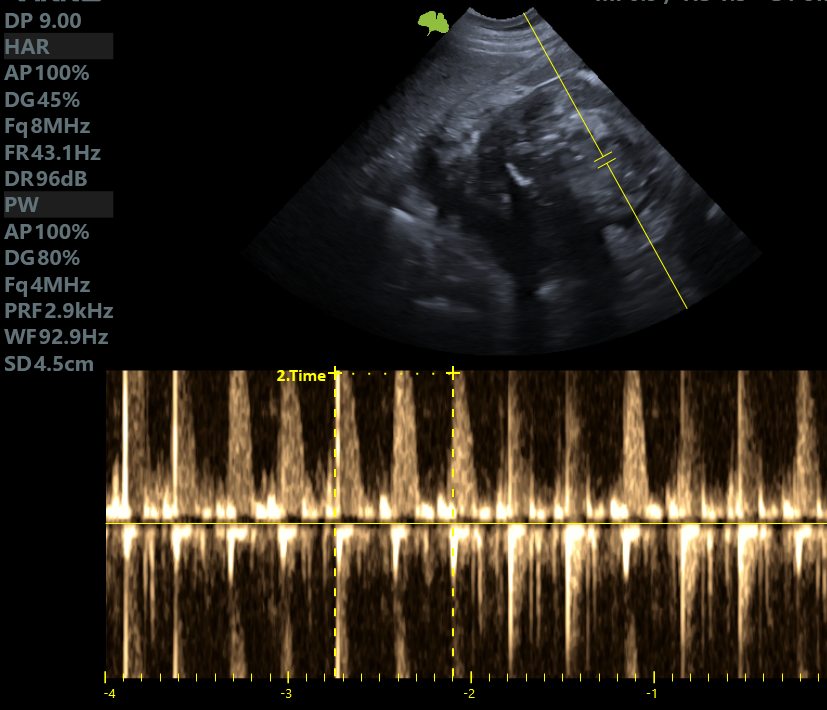

ZobaczKontrolne badanie USG pacjentki Weterynarii Dobieszowice. Serduszka biją prawidłowo, poród...